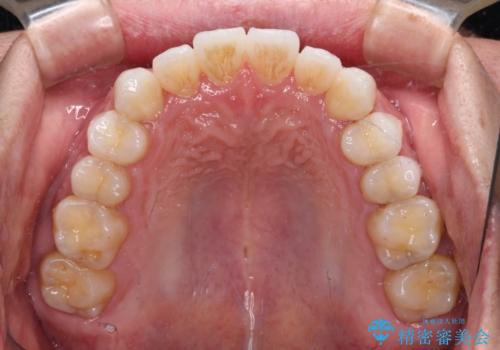

前歯のクロスバイトを改善 インビザラインによる矯正治療

- 前歯のクロスバイトを気にして来院された患者様です。

デコボコやクロスバイトが散見されたため、IPR(歯と歯の間を削る)によってスペースを獲得できるように設計し、インビザラインにより治療を行うこととしました。

今回は、ワイヤー装置を併用することなく治療を行い、トラブルなく、満足のいく歯列に整えることができました。

矯正治療の途中でホームホワイトニングを併用され、術前とは見違えるほどきれいな口元となりました。